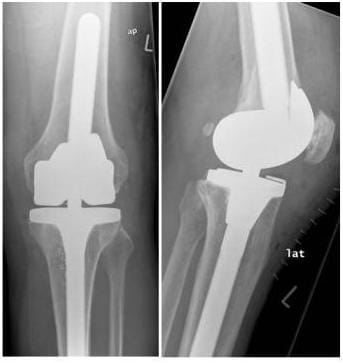

Die Prothesenimplantation wird anhand eines digitalen Röntgenbildes geplant (links), das Röntgenbild rechts zeigt die zugehörige Implantatlage eines bikondylären Oberflächenersatzes nach der Operation. (Bilder: Orthopädie)

Digitale Prothesenplanung

Postoperatives Resultat nach Versorgung mit Roboter assistierter Knieprothese mit Ausgleich des knöchernen Defektes durch Titan-Stufe auf der Innenseite.